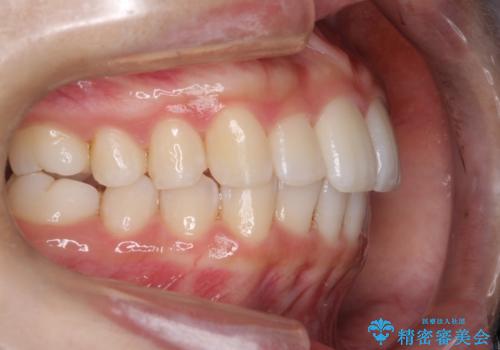

Invisalign インビザラインによる軽度なガタつきの改善

- 奥歯の位置関係はそこまで大きくいじらず、前歯群のみでガタつきの改善を計画しました

奥歯の位置関係に改善の余地はありますが、機能的に問題のない cusp to fossa の関係で咬めているため、前歯のガタつきを前歯のみで改善するというシンプルな計画で、短期間で治療を終了させました。